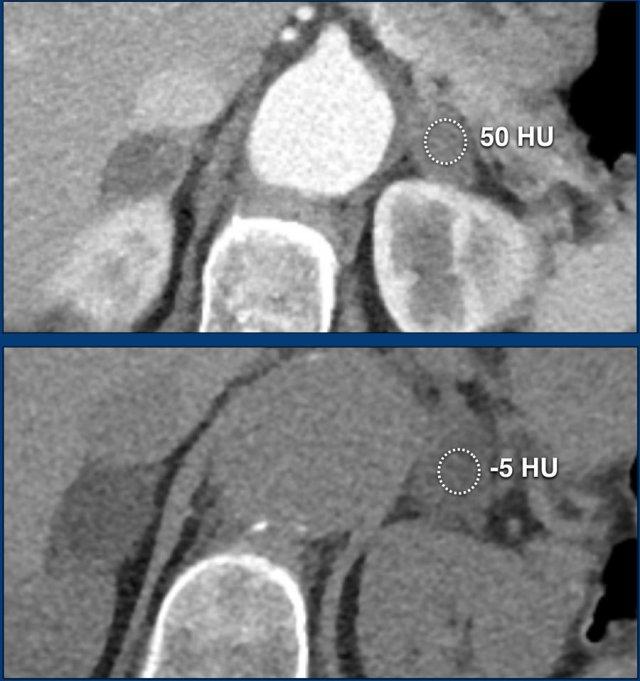

70% u tuyến chứa nhiều mỡ nội bào và sẽ có tỷ trọng thấp trên CT không tiêm thuốc cản quang [4,5].

Tỷ trọng bằng hoặc dưới 10 HU được coi là tiêu chuẩn chẩn đoán u tuyến giàu lipid.

Sử dụng ngưỡng an toàn 10HU trên CT không tiêm thuốc cho độ nhạy 70-79% và độ đặc hiệu cao 96-98% trong chẩn đoán u tuyến [5-7].

30% u tuyến thượng thận không chứa đủ lipid nội bào để có tỷ trọng dưới 10 HU và không thể phân biệt với các tổn thương không phải u tuyến trên CT không tiêm thuốc cản quang.

Các hình ảnh cho thấy u tình cờ tuyến thượng thận hai bên được phát hiện ở bệnh nhân 64 tuổi được chụp CT để phân tích phình động mạch chủ bụng.

Hình chụp pha động mạch cho thấy các tổn thương hai bên với tỷ trọng 50 HU.

Trên CT không tiêm thuốc thực hiện vài ngày sau, tỷ trọng ở cả hai tuyến thượng thận đều dưới 10 HU, xác nhận đây là các u tuyến giàu lipid.